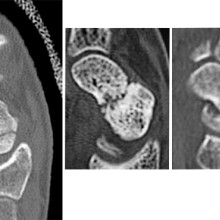

From left to right: Normal scaphoid fracture. Scaphoid fracture that is struggling to heal. Scaphoid non-union where the bone has failed to heal.